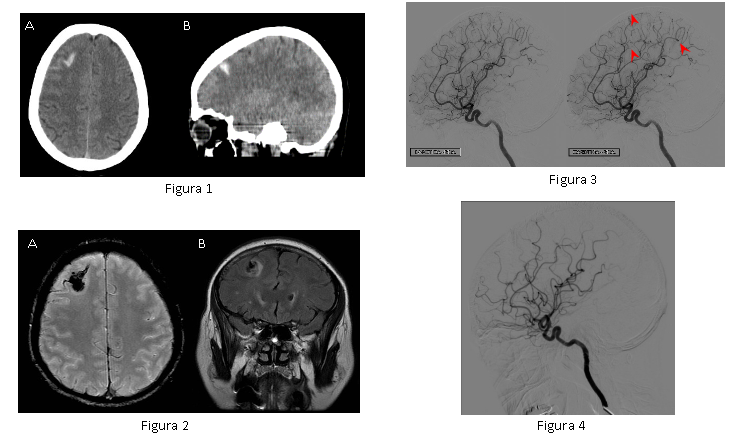

Figura 1. En las imágenes en plano transversal (A) y sagital (B) de CT cabeza sin contraste intravenoso, se observa un pequeño foco de hemorragia subaracnoidea y otro foco intraparenquimatoso en región frontal derecha.

Figura 2. Imágenes de RM secuencia T2* (A) y FLAIR (B) confirman la presencia del foco hemorrágico subaracnoideo e intraparenquimatoso asociado a edema vasogénico perilesional.

Figura 3. En la angiografía cerebral se observa vasoconstricción segmentaria de varios vasos de pequeño y mediano calibre de la arteria cerebral media y anterior (flechas rojas).

Figura 4. Angiografía cerebral de control realizada a los 6 meses, confirma la normalización del calibre de los vasos cerebrales.